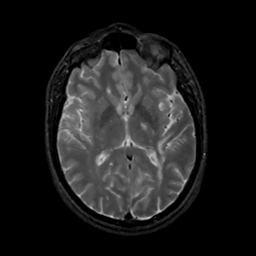

MR Study #16, June 23, 1991 -- Slice #26